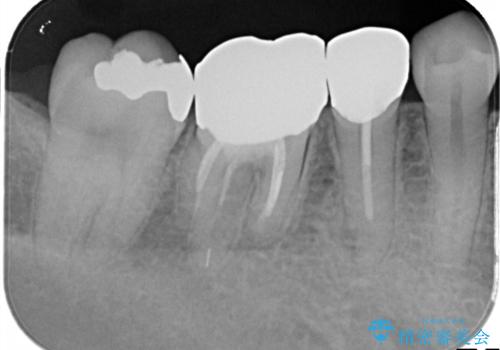

【メタルフリー】銀歯を白くしたい。オールセラミッククラウン。

- 銀歯を白くしたいと希望され来院されました。

すぐにでも白くしたいとのことで、2回目の来院で銀歯を白い仮歯に変更し喜んでいただきました。

根管治療は林先生に依頼しております。

ただ単純に白くするでけではなく拡大鏡を使用し、丁寧な処置を行なっております。